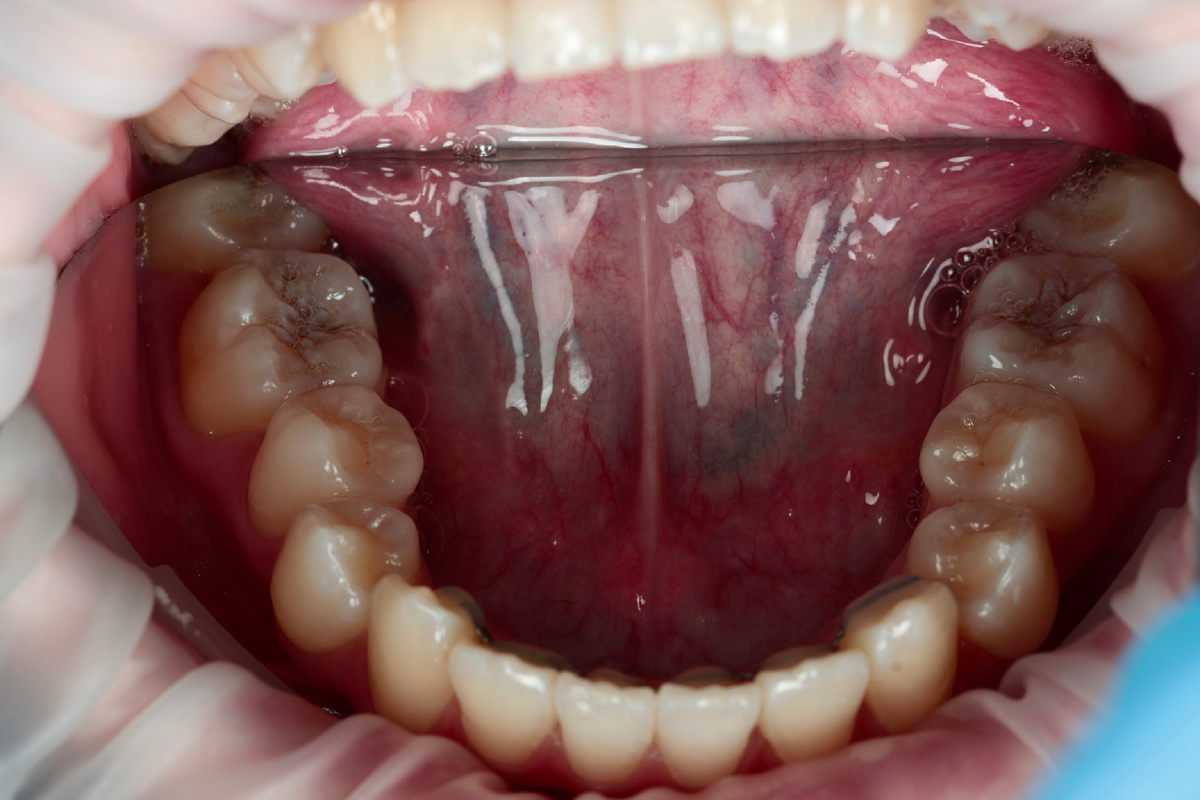

На первый взгляд, все выглядело очень прилично: фиссуры немного окрашены, но без видимых разрушений.

Фото не самое информативное для показа фиссур, но ниже будет видно более отчетливо